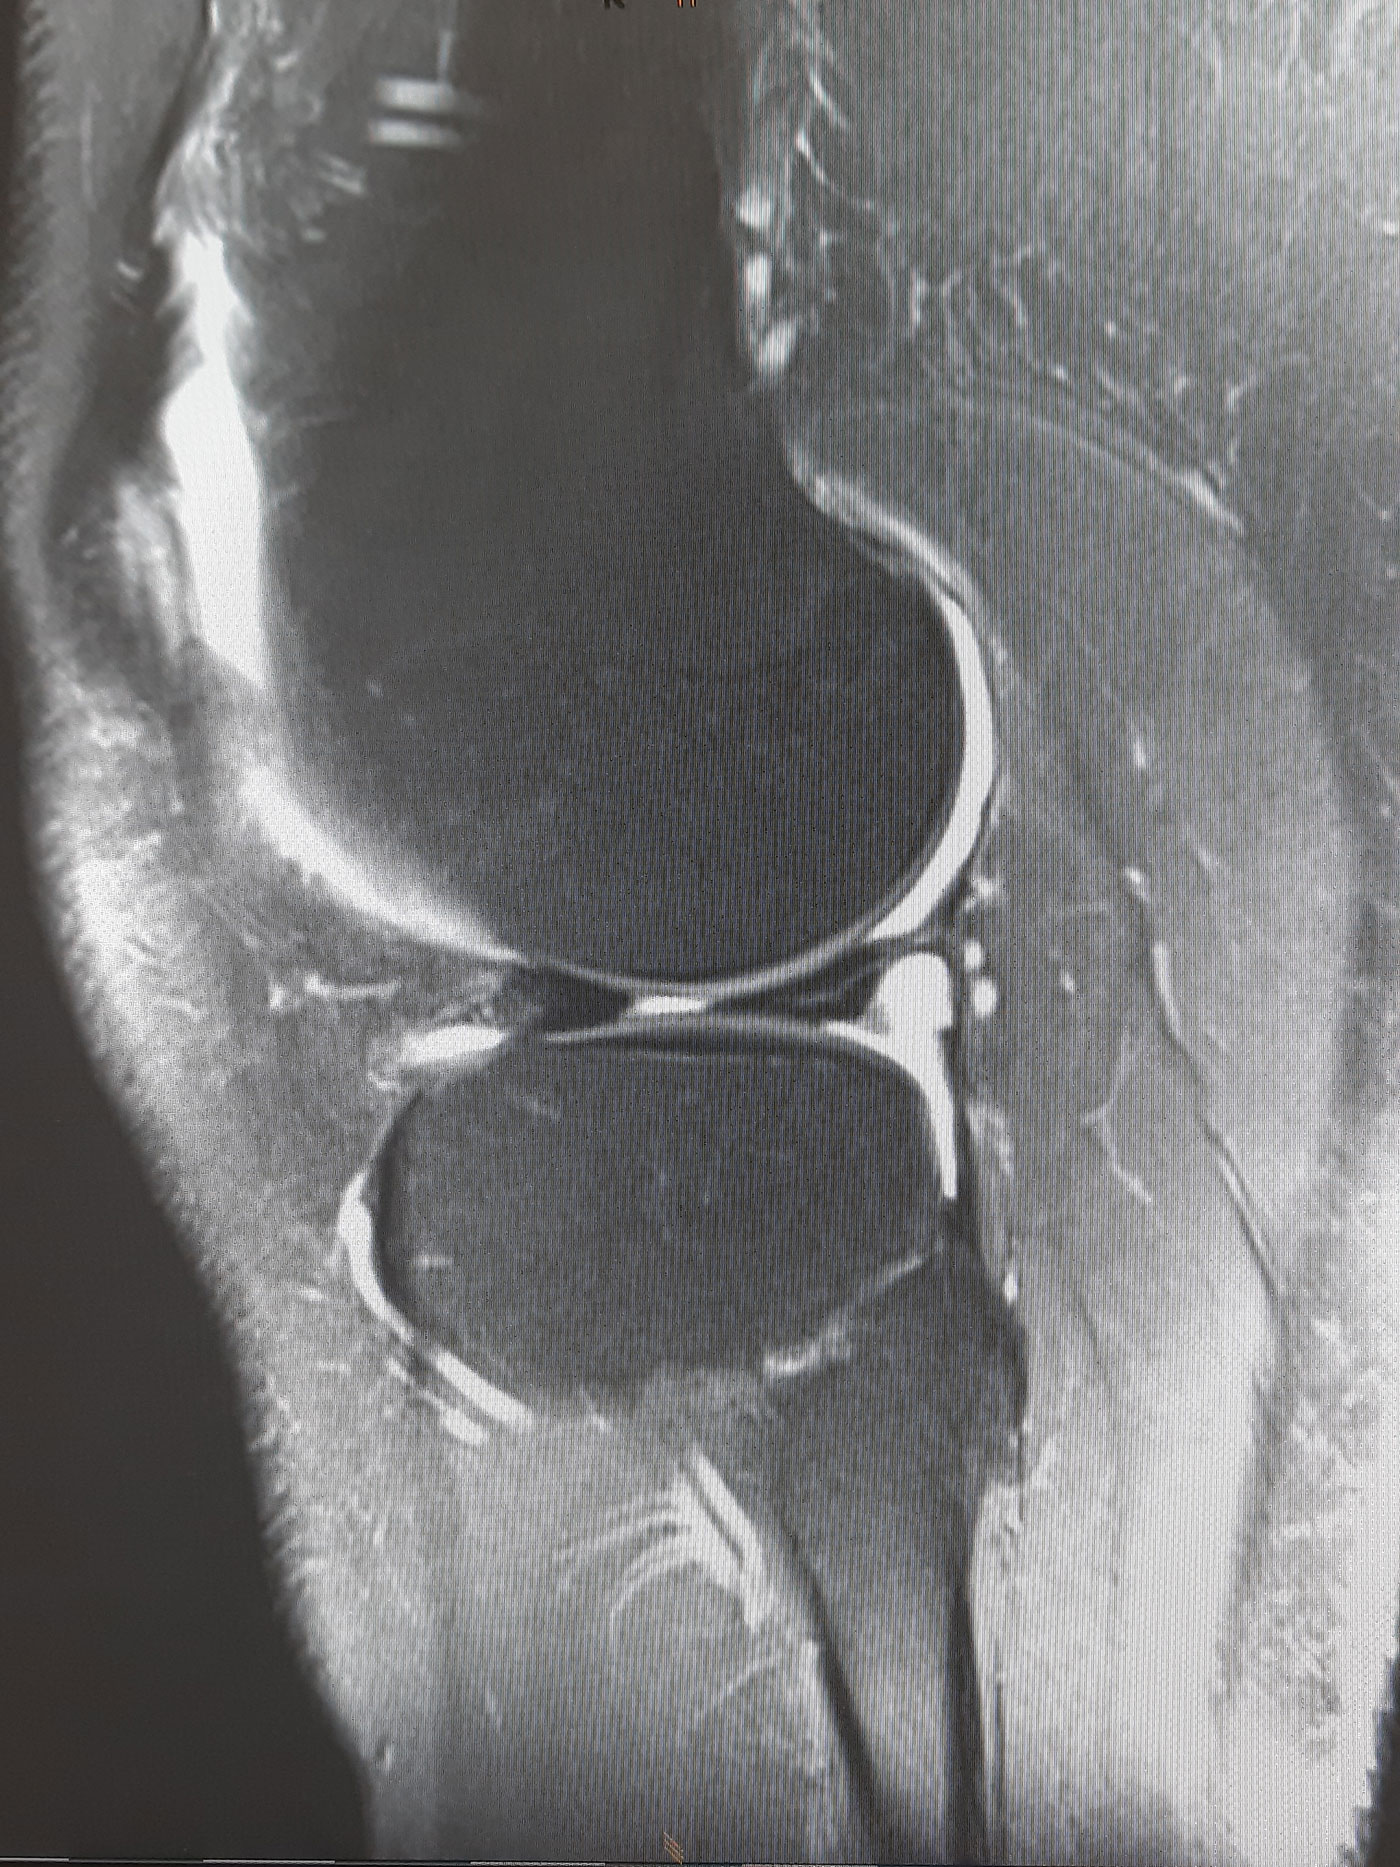

Standardmäßig werden Röntgenaufnahmen in zwei Ebenen sowie eine Ganzbeinstandaufnahme durchgeführt. Im Anschluss kann bei noch unklarem Knorpelzustand eine MRT-Untersuchung zur besseren Beurteilung des Schädigungsgrades des Knorpels erfolgen.

Bei fortgeschrittener Arthrose des Kniegelenks und entsprechendem Leidensdruck ist der künstliche Kniegelenksersatz die Therapie der Wahl. Dabei werden zunächst die geschädigten Knorpelanteile schablonenhaft entfernt und die Gelenkflächen mit Metallflächen ersetzt. Diese Metallflächen artikulieren über einen Mittelteil aus hochvernetztem Kunststoff, dem sogenannten Inlay.